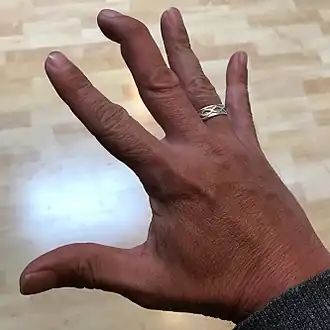

Ulnar claw hand occurs as a result of ulnar nerve damage, which instigates symptoms of numbness, pain, hand weakness, and difficulty to straighten fingers.[3]

Ulnar Claw Deformity

Due to flexion at the interphalangeal joints, and hyperextension at the metacarpophalangeal joints,[19] individuals' hand utility, such as grip, may be limited.[18] Note that damage to the ulnar nerve can also be triggered by a disease's onset.[12]